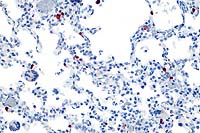

20x

obj

40x

- Case 22-1.Lung. Immunohistochemistry demonstrates

positive cells (red) stained for Rhesus cytomegalovirus antigen

occuring multifocally within alveolar septa. Note scattered alveolar

multinucleated giant (syncytial) cells.